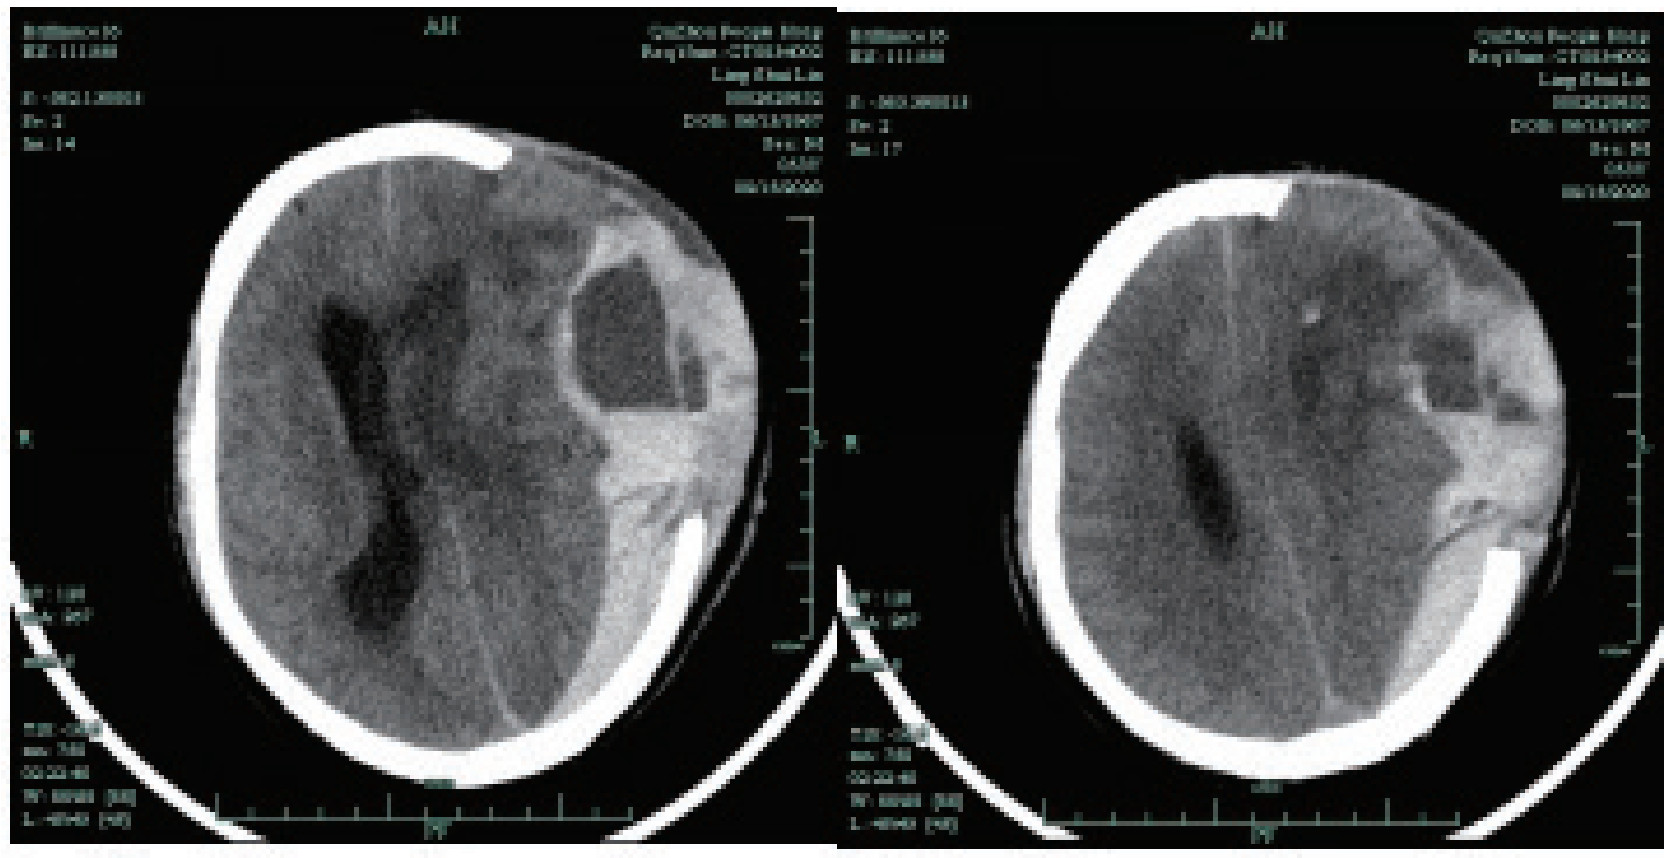

Lansberg[23]等认为VTE药物的预防降低了症状性DVT和肺栓塞的风险,而且对血肿扩大和病死率没有影响,但对LMWH的研究总体样本量偏少,而且是基于缺血性卒中的证据。Salvatore等[8]对各类开颅术后分低、中、高危DVT患者使用不同疗程的LMWH进行抗凝(2~14 d),其总显著出血概率为0.3%,未有增加术后出血概率,但该研究并未统计预防剂量的LMWH导致自发性脑出血术后颅内再出血率以及DVT发生率。本研究的患者均为自发性脑出血术后,排除了其他原因的开颅手术,在使用IPC联合LMWH治疗组中发生颅内再出血1例(2.22%),与对照组再出血发生率相比较,差异无统计学意义(P<0.05)。本例颅内再出血发生的时间在LMWH皮下注射第5天,当时因皮下脑积水行穿刺抽液,在抽液过程后期出现血性液,12 h后出现脑疝(CT见图 2),究其原因可能是穿刺导致小血管破裂出血增多而死亡,而非典型抗凝后颅内再出血表现。对此,笔者认为在低分子肝素使用期间应尽量避免类似有创操作,防止严重情况的发生。

|

| 图 2 治疗组颅内再出血患者CT影像 |